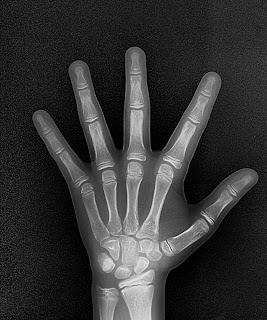

Carpal                                                                Seios da Face